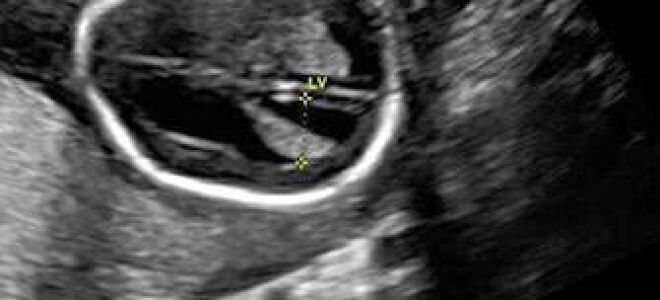

Вентрикуломегалия у грудничка: что это и насколько опасно?

Вентрикуломегалия у плода – патология, характеризующаяся увеличением в размерах мозговых желудочков.